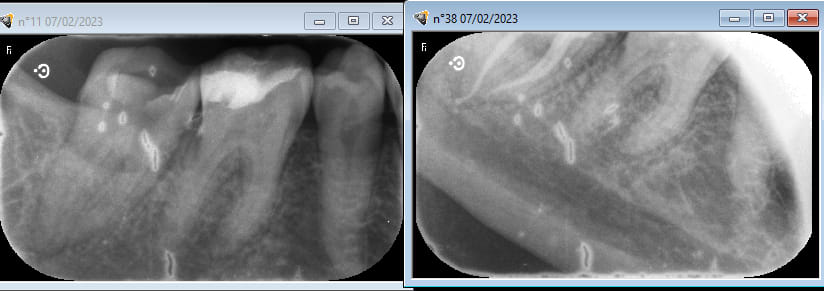

mes radios pourries avant , après endo .

pas évident sur mes radio à la con qu il y ait embrouille en 46 .

certes le compo sur 46 et 47 sont pipés , mais pas plus que ça . je ne sais pas de quand ça date , c est la 1ere fois que je la voyais